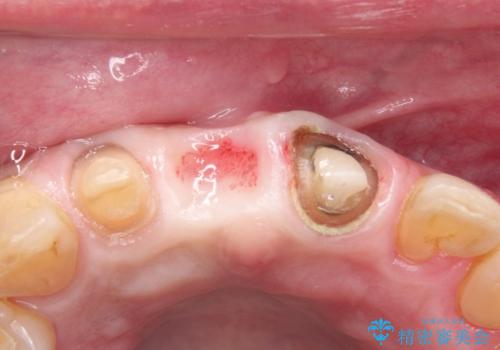

- 矯正治療終了後の患者様です。

前歯が欠損しており、ブリッジでの修復を希望されましたので、オールセラミッククラウン(スタンダード)で治療を行いました。